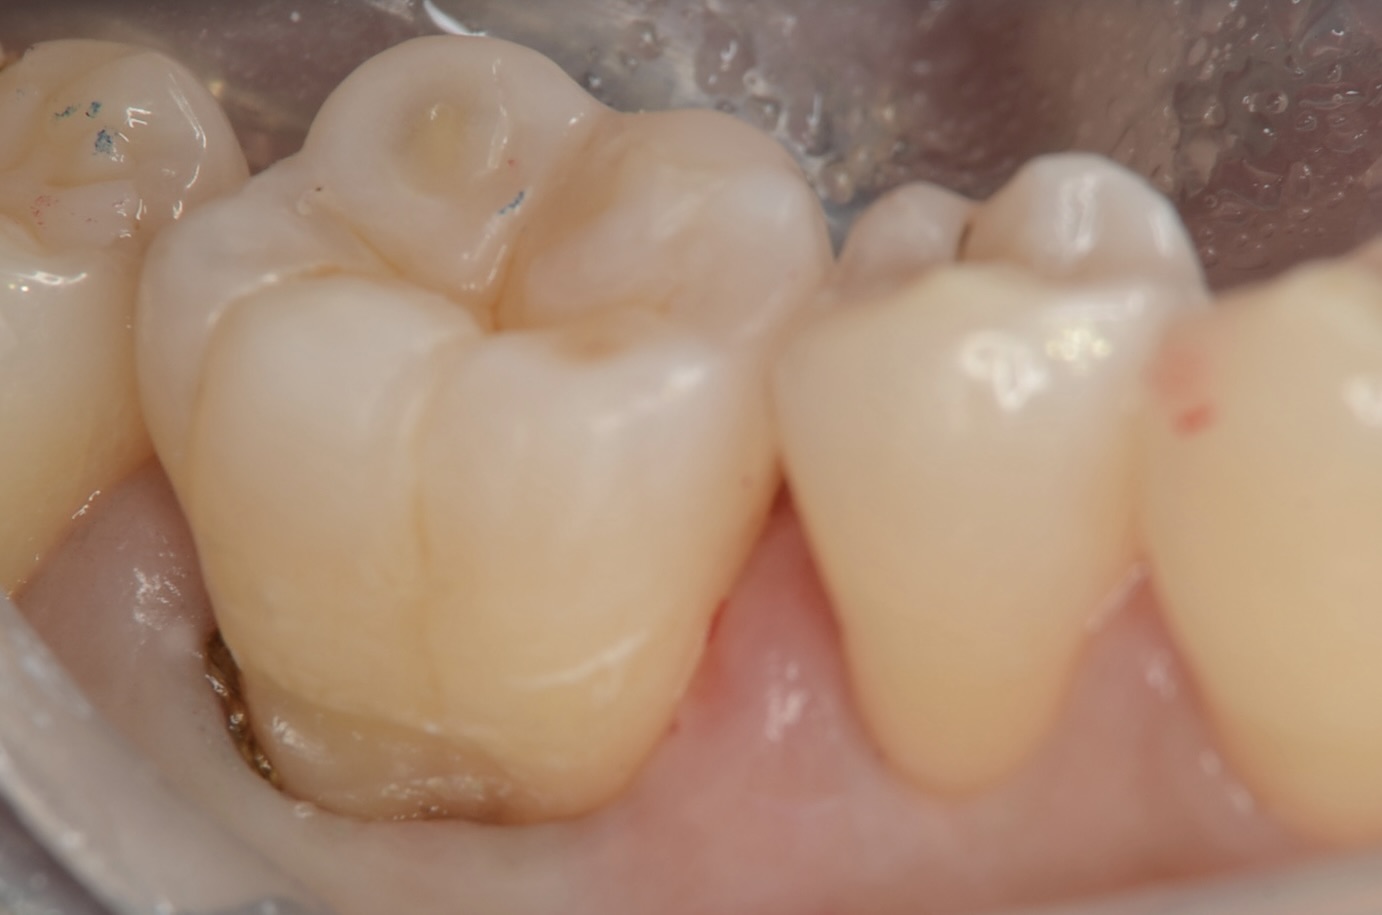

レジン充填

天然歯の自然な形態を模倣して修復しました。 -

舌側面観

滑らかに仕上がっています。 -

頬側面観